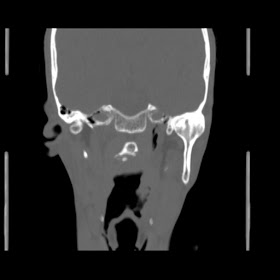

O/E images:

patient New hrct investigation images is: